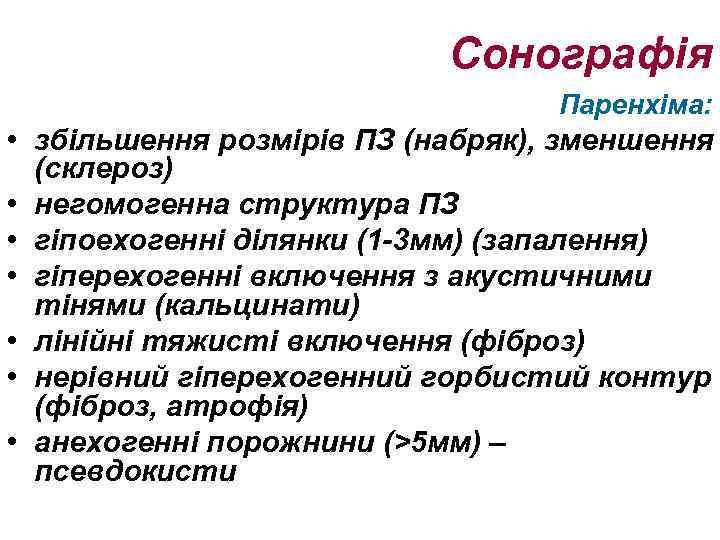

Сонографія Паренхіма: • збільшення розмірів ПЗ (набряк), зменшення (склероз) • негомогенна структура ПЗ • гіпоехогенні ділянки (1 -3 мм) (запалення) • гіперехогенні включення з акустичними тінями (кальцинати) • лінійні тяжисті включення (фіброз) • нерівний гіперехогенний горбистий контур (фіброз, атрофія) • анехогенні порожнини (>5 мм) – псевдокисти

Сонографія Паренхіма: • збільшення розмірів ПЗ (набряк), зменшення (склероз) • негомогенна структура ПЗ • гіпоехогенні ділянки (1 -3 мм) (запалення) • гіперехогенні включення з акустичними тінями (кальцинати) • лінійні тяжисті включення (фіброз) • нерівний гіперехогенний горбистий контур (фіброз, атрофія) • анехогенні порожнини (>5 мм) – псевдокисти